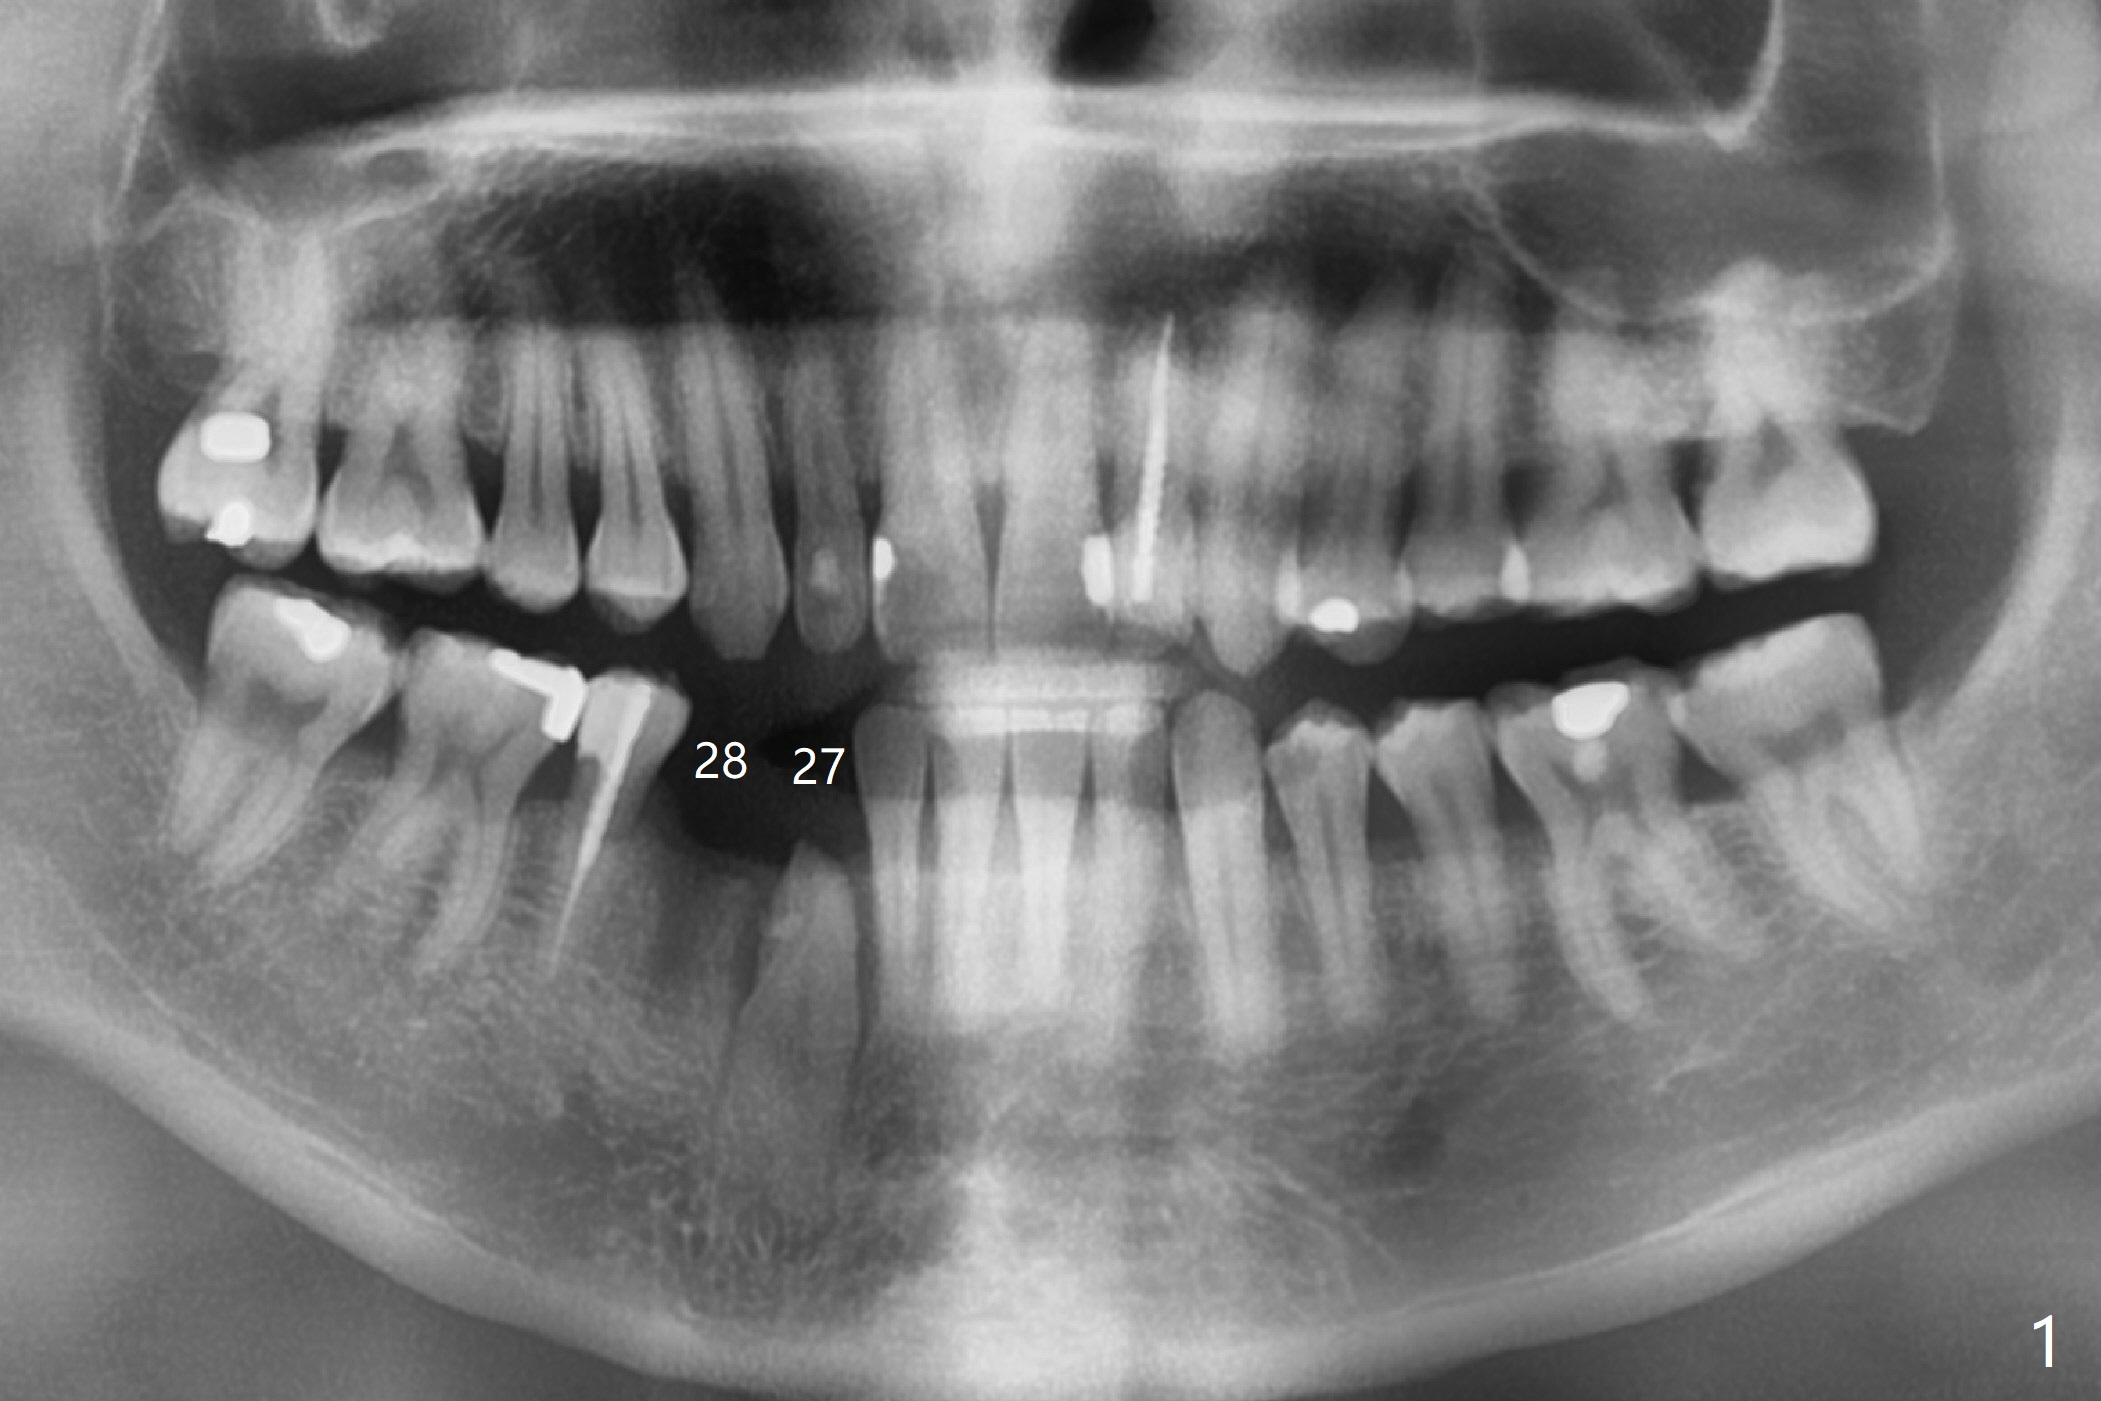

A 30-year-old man requests orthodontic extrusion of the impacted lower right canine and implant at the next site (Fig.1). Since the canine rotates with wider mesiodistal width of the crown (Fig.2 red line), the implant should be smaller and placed distal (Fig.2 red arrow). The extrusion will gain the bone to the distal surface of the lateral incisor (Fig.2, 3*). In fact the tooth #27 is malformed in that the root is split (Fig.4, as compared to the tooth #22 (Fig.5)). Surgical guide will be used for precision.